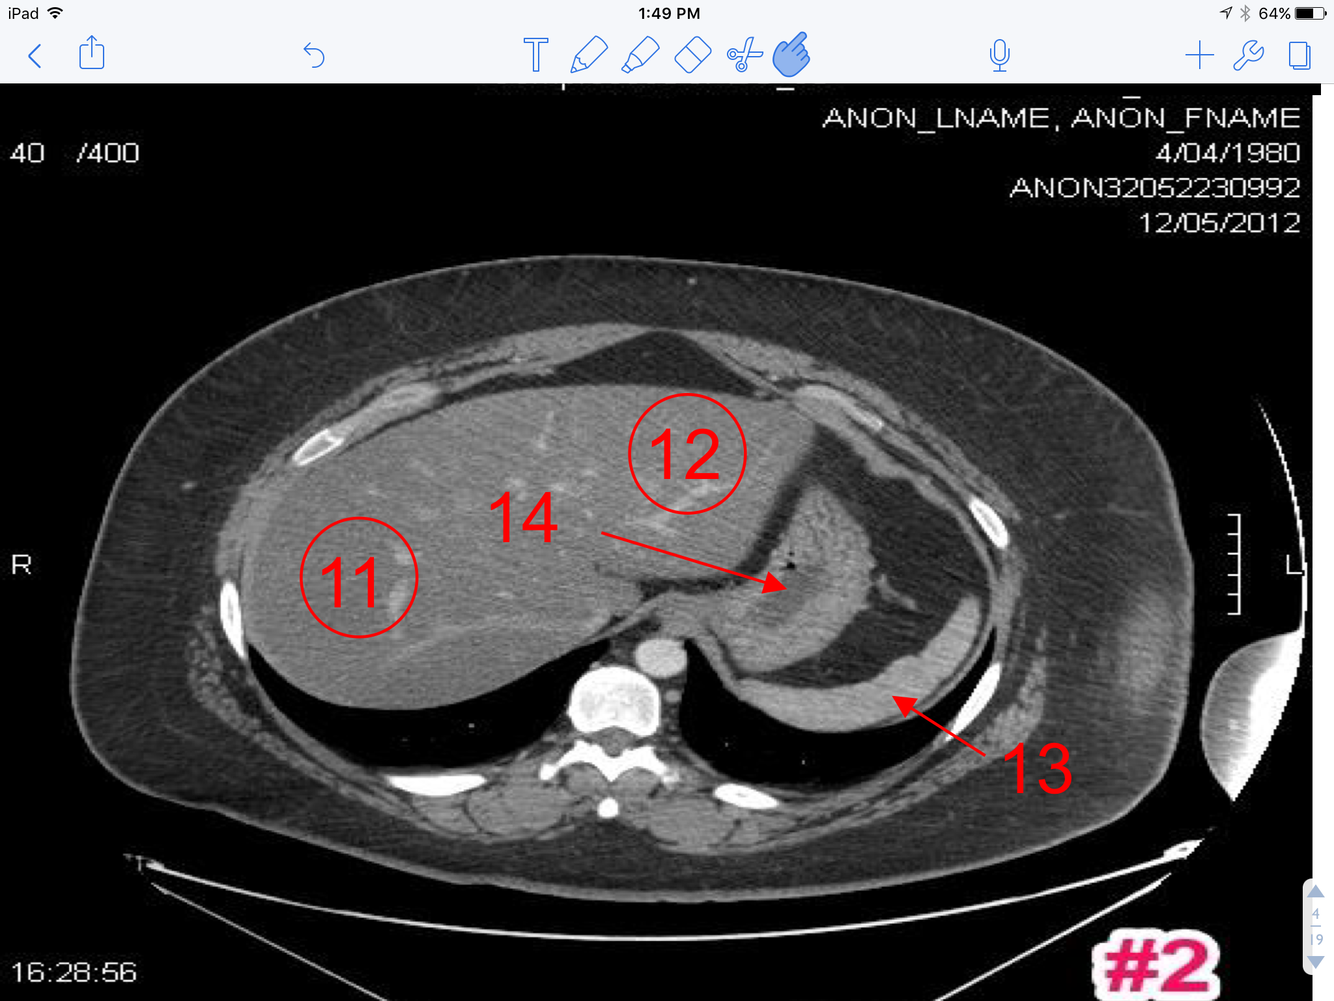

3

Q

A

1. Branches of the Lt. branch of the portal vein

2. Hemiazygos vein

4

1. Ligamentum teres (fissure for)

2. Splenic flexure

3. Splenic vessel

4. Tail of the Pancreas

5. Rt & Lt crus of diaphragm

6. Lt branch of portal vein

7. Rt branch of the portal vein

8. Intrahepatic inferior vena cava